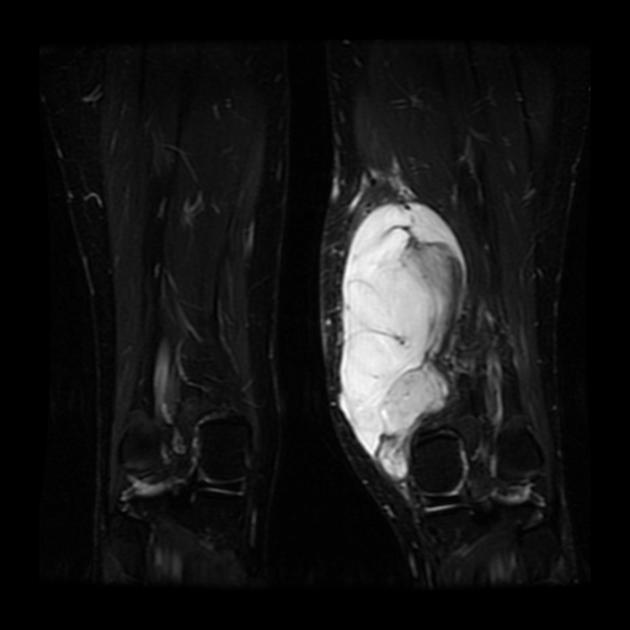

Липосаркома На Бедре Фото 117 фотографий